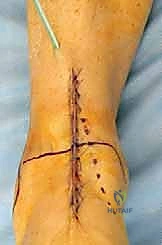

1. الشق الجراحي والوصول للمفصل

يقوم الجراح بإجراء شق أمامي طولي (Anterior Approach) في منتصف الكاحل. يتم إبعاد الأوتار والأوعية الدموية والأعصاب بعناية فائقة (هنا تتجلى أهمية مهارات الجراحة الدقيقة التي يمتلكها الدكتور هطيف) للوصول إلى محفظة المفصل.